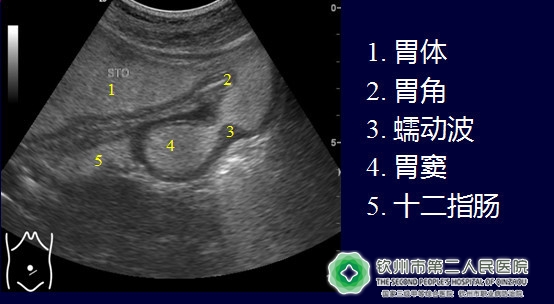

(其中一部分正常胃结构,真的好清晰啊!)

(1)肿瘤:

良性肿瘤:息肉、间质瘤等。

恶性肿瘤:胃癌、恶性淋巴瘤、转移瘤等。

(胃间质瘤)

(胃息肉)

(乙状结肠肿瘤)

(2)炎症:

急慢性胃炎、胃溃疡、胃壁旁脓肿。

(十二指肠球溃疡)

(胃炎(胃壁弥漫性增厚))